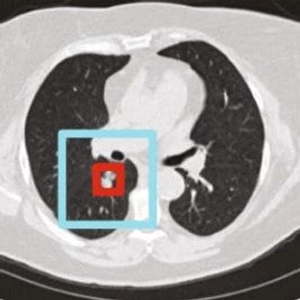

谷歌发表在Nature Medicine上的一项新研究,让人类解决肺癌难题前进了一大步。在这项研究中,AI能够根据患者的胸部CT图像,诊断出早期肺癌,与六位放射科医生相比,AI的准确度更高,检测到的病例增加了5%,假阳性减少了11%,AUC达到94.4%。

癌症ROI检测,构建RetinaNet47,找出病灶区域。